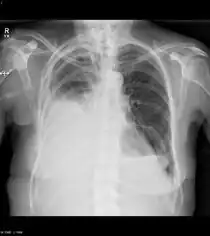

- Metastatic breast cancer to the lung or pleura causes chronic cough, dyspnea, abnormal chest X-ray, and chest pain.

In the detection of bone metastases, skeletal scintigraphy (bone scan) is very sensitive and is recommended as the first imaging study in asymptomatic individuals with suspected breast-cancer metastases.[17] X-ray radiography is recommended if there is abnormal radionuclide uptake from the bone scan and in assessing the risk of pathological fractures, and is recommended as the initial imaging study in patients with bone pain.[17] MRI or the combination PET-CT may be considered for cases of abnormal radionuclide uptake on bone scan, when radiography does not give an acceptably clear result.[17]